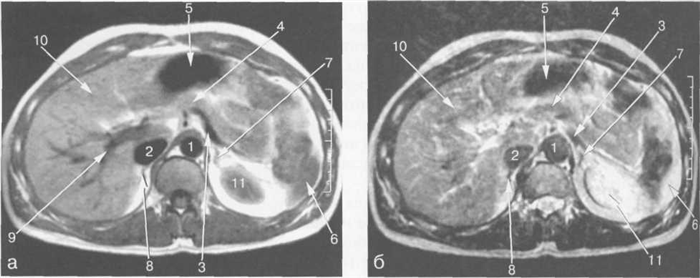

Рис. 11.24. MPT брюшной полости в аксиальной плоскости на уровне надпочечников.

а-Т1-ВИ;б-Т2-ВИ.

1 — аорта; 2 — нижняя полая вена; 3 — селезеночная артерия; 4 — общая печеночная артерия; 5 — чревный ствол; 6 — левый надпочечник; 7 — правый надпочечник; 8 — левая почка; 9 — желчный пузырь; 10 — Бертиниевы столбы левой почки.